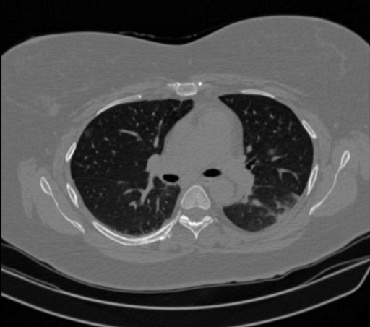

It should be mentioned that for explainability purposes [7, 8, 9], an anchor set was generated for the COV19-CT-DB database [5]. This included 11 anchors, each representing a respective 3-D CT scan obtained through an appropriate clustering procedure. Figure 2 shows a series of slices from a COVID-19 case, whereas Figure 3 shows a series of slices from a non COVID-19 case.